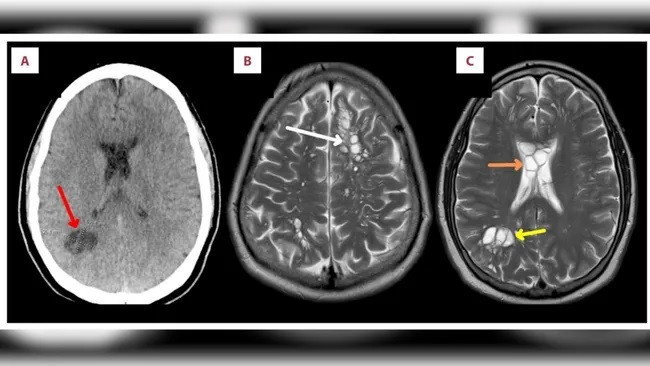

| Kết quả quét não của người đàn ông cho thấy nhiều khối ấu trùng sán dây lợn phát triển ở các phần khác nhau trong não. (Ảnh: Byrnes E, Shaw B, Shaw R, Madruga M, Carlan SJ). |

Tại phòng khám, kết quả chụp cắt lớp vi tính (CT) cho thấy người đàn ông này có nhiều u nang bên trong chất trắng, hay còn gọi là dây cách điện, trong não - đặc biệt là các sợi thần kinh nằm sâu bên trong. Người đàn ông này có một cụm u nang đáng chú ý ở góc dưới bên phải của não. Các bác sĩ đã cho người đàn ông này nhập viện luôn.

Tại bệnh viện, kết quả chụp cộng hưởng từ (MRI) cho thấy có thêm các u nang ở phần trước và phần giữa của lớp ngoài não, cũng như tình trạng sưng tấy, điều này càng khẳng định chẩn đoán bệnh u nang thần kinh.